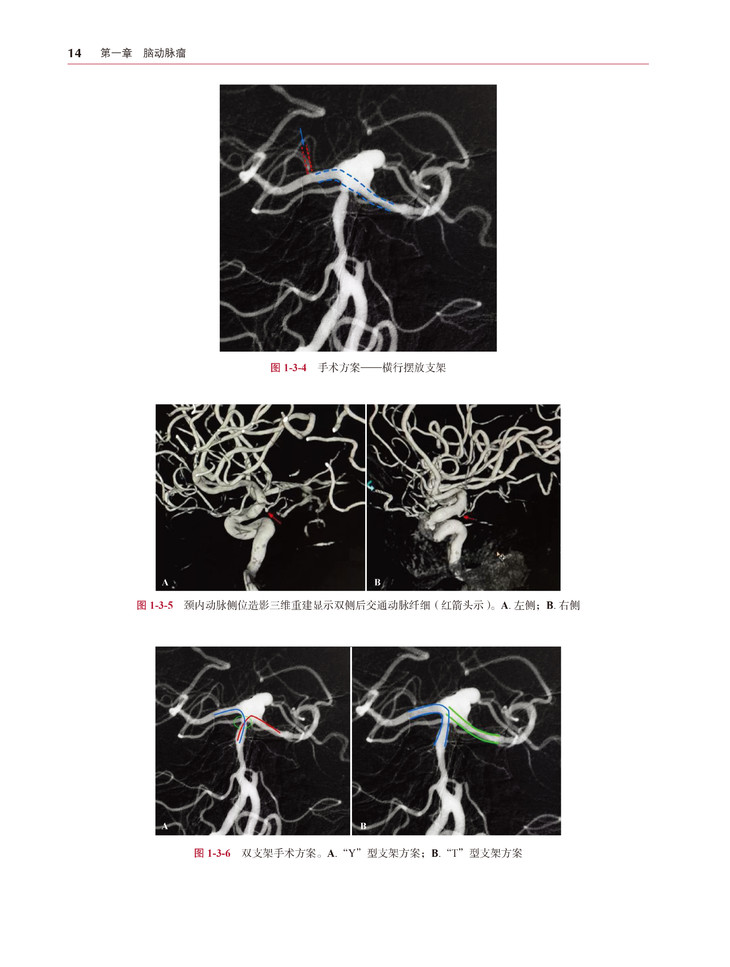

本书是一本介绍神经介入治疗相关病例的专业书籍,作者都是来自神经介入领域的知名专家。本书所选择的病例范围广泛并且具有代表性,共包括脑动脉瘤、脑血管畸形、脑血管急性闭塞、脑血管慢性狭窄及闭塞、特殊病例五个部分。所有病例均有相应介绍,包括患者的临床表现、影像学检查、手术操作、病例讨论等。

本书作者们通过丰富的实践经验和理论知识,对病例及手术治疗进行了生动介绍。书中包含了大量的影像图片和插图,能够为读者直观地呈现病